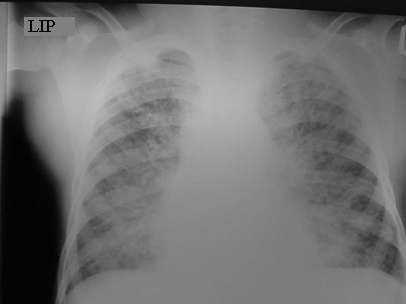

Diagnosis: CXR usually shows focal abnormalities with bronchial dilatation as shown in the figure below. TB may have a similar radiological picture to bronchiectasis and in a high TB burden area where there is over-reliance on radiological diagnosis for PTB, bronchiectasis may be missed or frequent retreatments of TB may occur. Almost a quarter of a cohort of children with HIV-related bronchiectasis in one study received two courses of antituberculosis treatment. In a high TB burden area, the differential diagnosis of an abnormal chest X-ray in children with chronic cough or previously treated TB should include bronchiectasis.

Where available a High-resolution computed tomography (HRCT) scanning is the standard test for diagnosis especially in the absence of characteristic chest radiograph findings of dilated airway, with thickened airway walls. Key features on CT scan: Enlarged internal bronchial diameter with bronchi that appear larger than the accompanying artery. Other findings include the failure of the larger airways to taper while progressing to the lung periphery, air fluid levels in the dilated airways, and the identification of airways in the extreme lung periphery. Other testing may be indicated to diagnose underlying conditions.